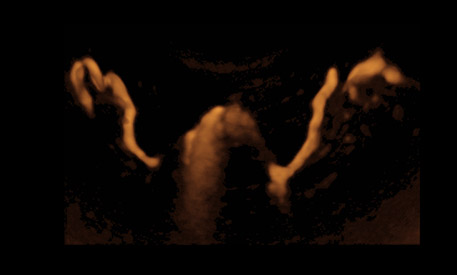

Die Beurteilung der Eileiter kann statt über eine Bauch­spiegelung auch mit einer zwei- oder dreidimensionalen Ultraschall­untersuchung (HyCoSy) erfolgen. Dabei werden die Eileiter im Rahmen eines gynäkologischen Ultraschalls mit einer natürlichen Gellösung gespült und im Ultraschall­bild sichtbar gemacht. Gleichzeitig ermöglicht die HyCoSy es, die Gebär­mutter auf Veränderungen wie Polypen oder Myome hin zu untersuchen. Die Ultraschall­darstellung ist ein nicht-operatives, schonendes Verfahren und erfolgt ambulant mit einer leichten, etwa 5-minütigen Schlafnarkose.

Die dreidimensionale Ultraschalluntersuchung HyCoSy erlaubt es im Gegen­satz zum zwei­dimensionalen Ultraschall, die Eileiter in ihrer vollen Länge im kleinen Becken zu beurteilen. Mit der herkömmlichen, zwei­dimensionalen Ultraschall­untersuchung hingegen sind die Eileiter häufig nicht in ihrer vollen Länge zu verfolgen. Insbesondere der Fimbrien­trichter, also das Ende des Eileiters, entzieht sich der herkömmlichen zwei­dimensionalen Ultraschalluntersuchung. Deshalb wenden wir an unserem Zentrum ausschließlich das modernste 3D-Kontrast­sonographie-Verfahren an.

Kinderwunschbehandlung Ultraschallkontrastuntersuchung

Moderne Computer-Technologien ermöglichen eine sehr genaue Untersuchung der Eileiter per Ultraschall.